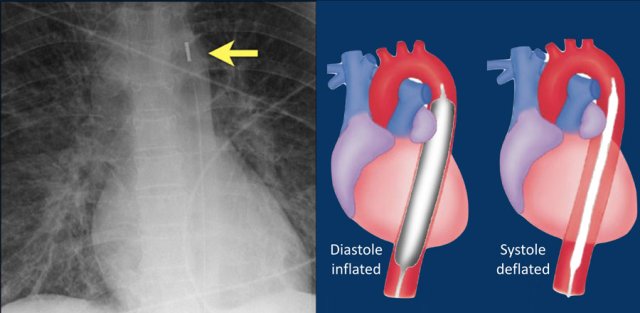

Intra-aortic balloon pump

The intra-aortic balloon pump (IABP) is a mechanical device that increases myocardial oxygen perfusion and indirectly increases cardiac output through afterload reduction.

It consists of a cylindrical polyurethane balloon that sits in the aorta, approximately 2 centimeters (0.79 in) from the left subclavian artery.

The balloon inflates and deflates via counter pulsation, meaning it actively deflates in systoleand inflates in diastole.

Systolic deflation decreases afterload through a vacuum effect and indirectly increases forward flow from the heart.

Diastolic inflation increases blood flow to the coronary arteries via retrograde flow.

These actions combine to decrease myocardial oxygen demand and increase myocardial oxygen supply (reference).